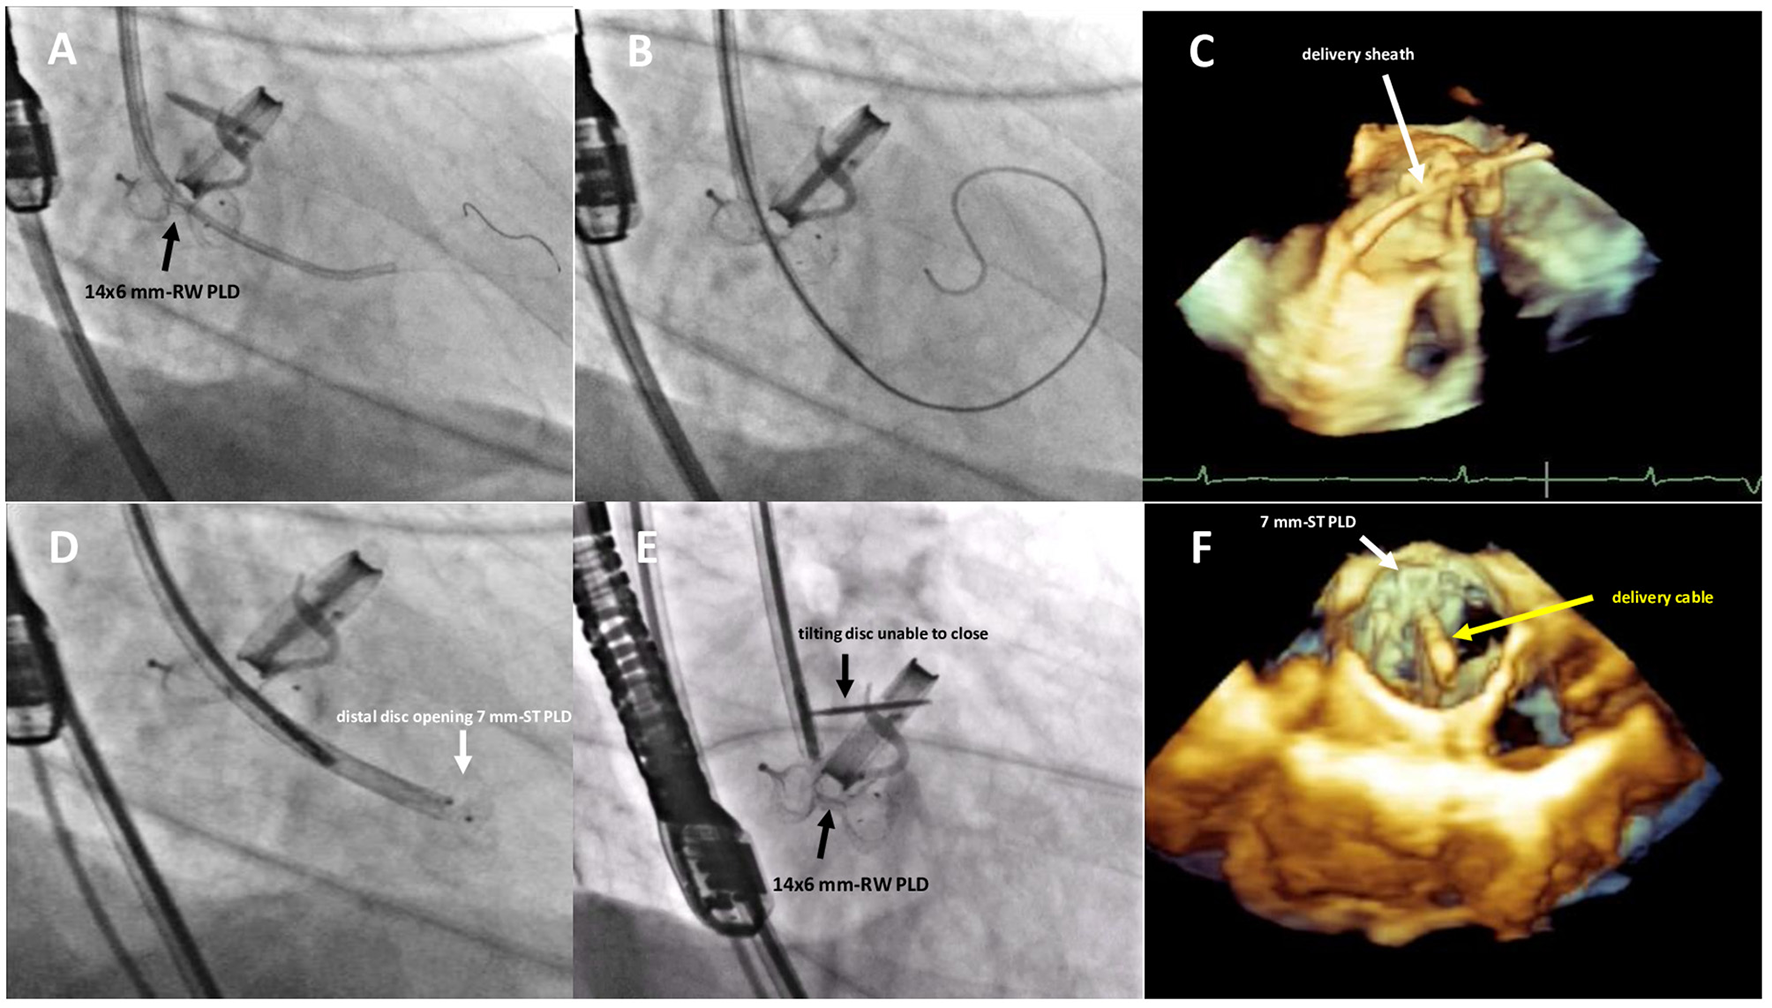

Figure 3

Fluoro-angiographic and real-time 3D TEE procedural steps showing the crossing of the residual leakage in close proximity of the already implanted 14 × 6 mm rectangular waist PLD (A–C), the distal disc opening of the 7 mm square twist PLD (D) still anchored to the delivery cable and the inference with the tilting disc of the mechanical aortic valve (E,F). RW, rectangular waist; ST, square twist.